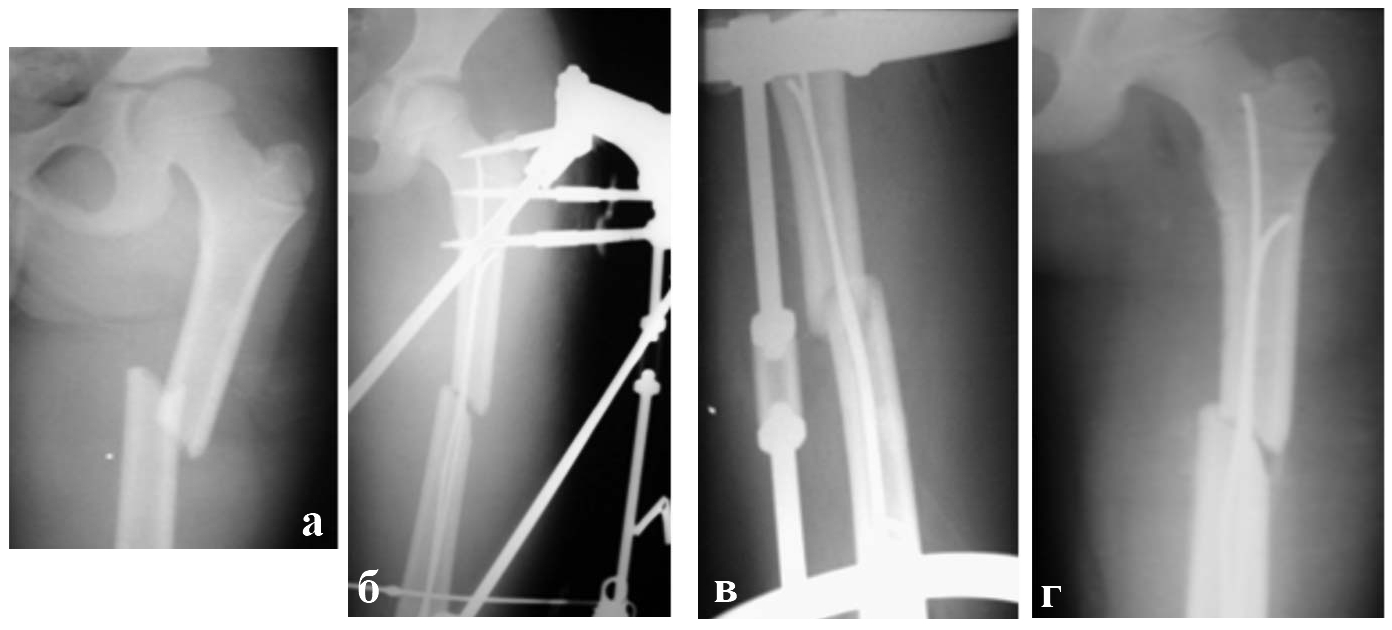

Второй клинический пример, Больная К., 7 лет. Диагноз: закрытый «бамперный» перелом диафиза бедренной кости с полным смещением отломков. (Рис. 3-5)

Наличие интерпозиции мягких тканей стало показанием для открытого остеосинтеза облегченным аппаратом Илизарова с интрамедуллярным армированием спицами с биоактивным ГА покрытием. Первые признаки репаративной регенерации кости на рентгенограммах бедра появились через 3 недели и на 25 день фиксации аппарат Илизарова был демонтирован. Через 1,5 месяца девочка уже приступила к регулярным тренировкам художественной гимнастики.

Рис. 3. Рентгенограммы бедра пациентки К.,7 лет:

а - до операции;

б, в - в день остеосинтеза;

г - через 21 день после операции.